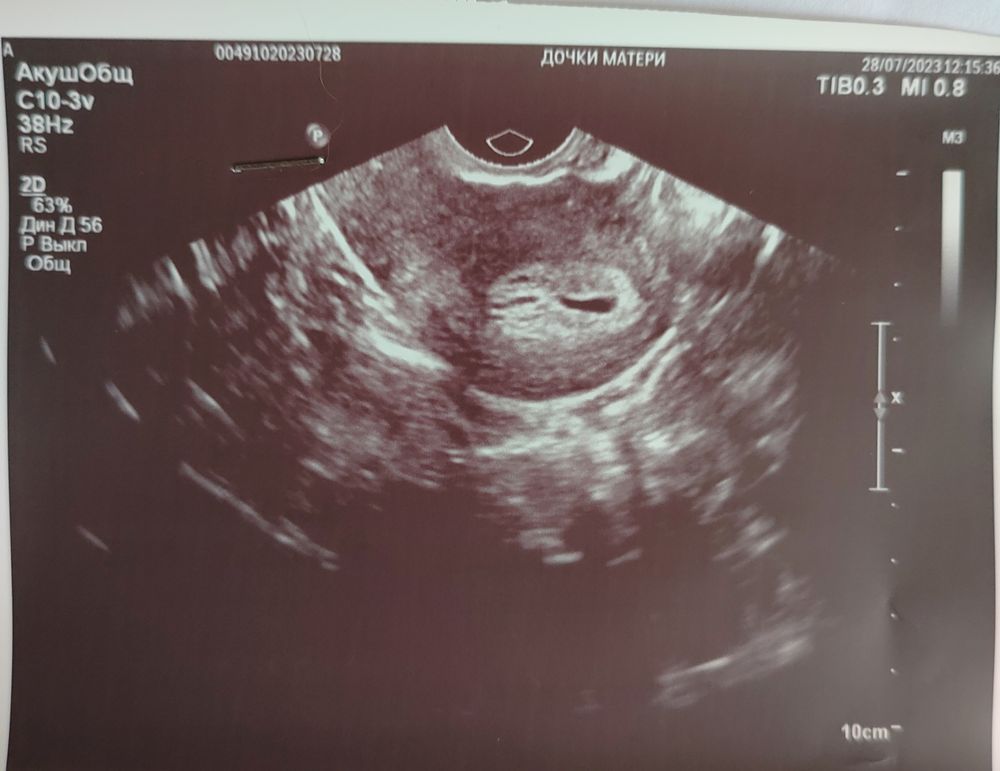

Беременность или гематомы

Мне кажется все у вас хорошо и просто срок маленький. А так очень похоже на пя

Мне кажется либо узист, либо аппарат не очень, у меня увидели ПЯ 1,5 мм на 19 дпо, ХГЧ был на 18 дпо 557 Изображение Длинная чёрная полоска сказали жидкость, это норма, на следующем УЗИ она пропала Изображение

Вообще очень похоже на ПЯ, да и результат хгч достойный. Сходите на УЗИ дней через 5, уже будет все понятно, думаю